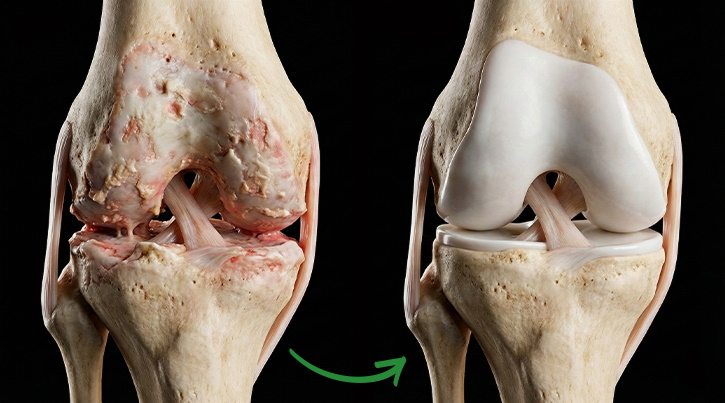

INFLAMACIÓN

Etapa inicial de la enfermedad

ADELGAZAMIENTO DEL CARTÍLAGO

Pérdida de protección

FRICCIÓN ÓSEA

Dolor en los huesos

DEFORMACIÓN

Ya es irreversible

PASO 1: TU SITUACIÓN ACTUAL

Lo que sientes:

Crujido

Dolor leve después del esfuerzo.

Rigidez matutina.

Lo que realmente ocurre en el interior:

Cada día mueren cientos de células del cartílago.

Este se va adelgazando, como una suela desgastada.

Esta es la última etapa en la que el proceso aún es reversible.

PASO 2: SENTENCIA PARA TU ARTICULACIÓN

Así es como se ve el punto sin retorno.